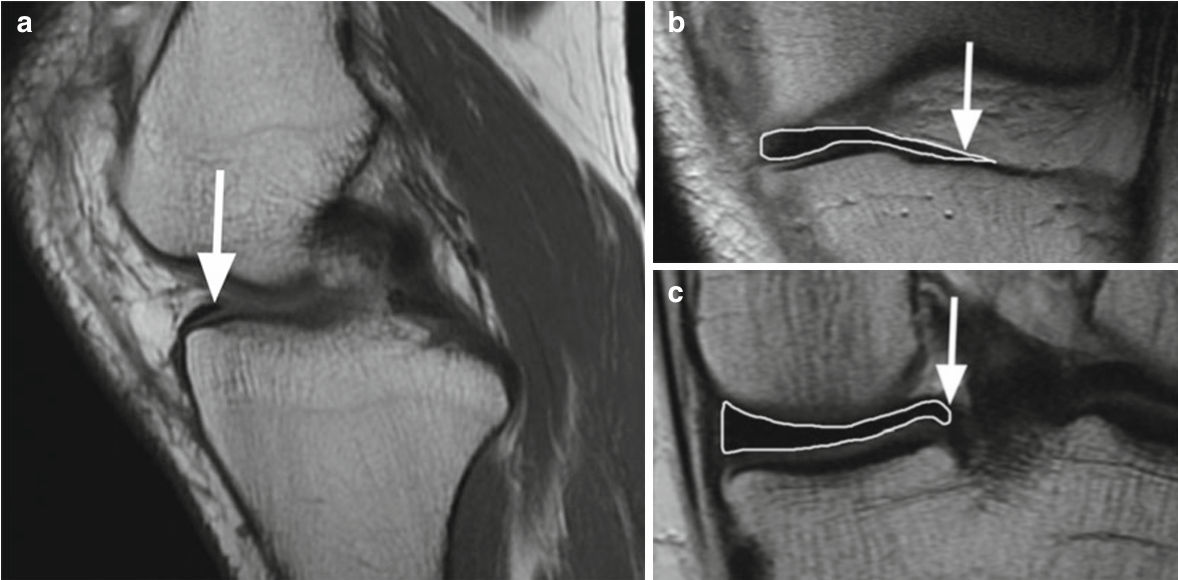

Fig. 5.2 Ligamentos meniscofemorales y meniscotibiales en un varón de 22 años. La imagen FSE de densidad de protones coronales (PD) muestra el ligamento meniscofemoral insertado en el cóndilo femoral y el margen superior del cuerpo del menisco medial (flecha grande) y el ligamento meniscotibial más corto (flecha pequeña) que conecta el margen inferior del menisco medial con la tibia. Ambos ligamentos son estructuras de la capa profunda del ligamento colateral medial (flecha curvada)